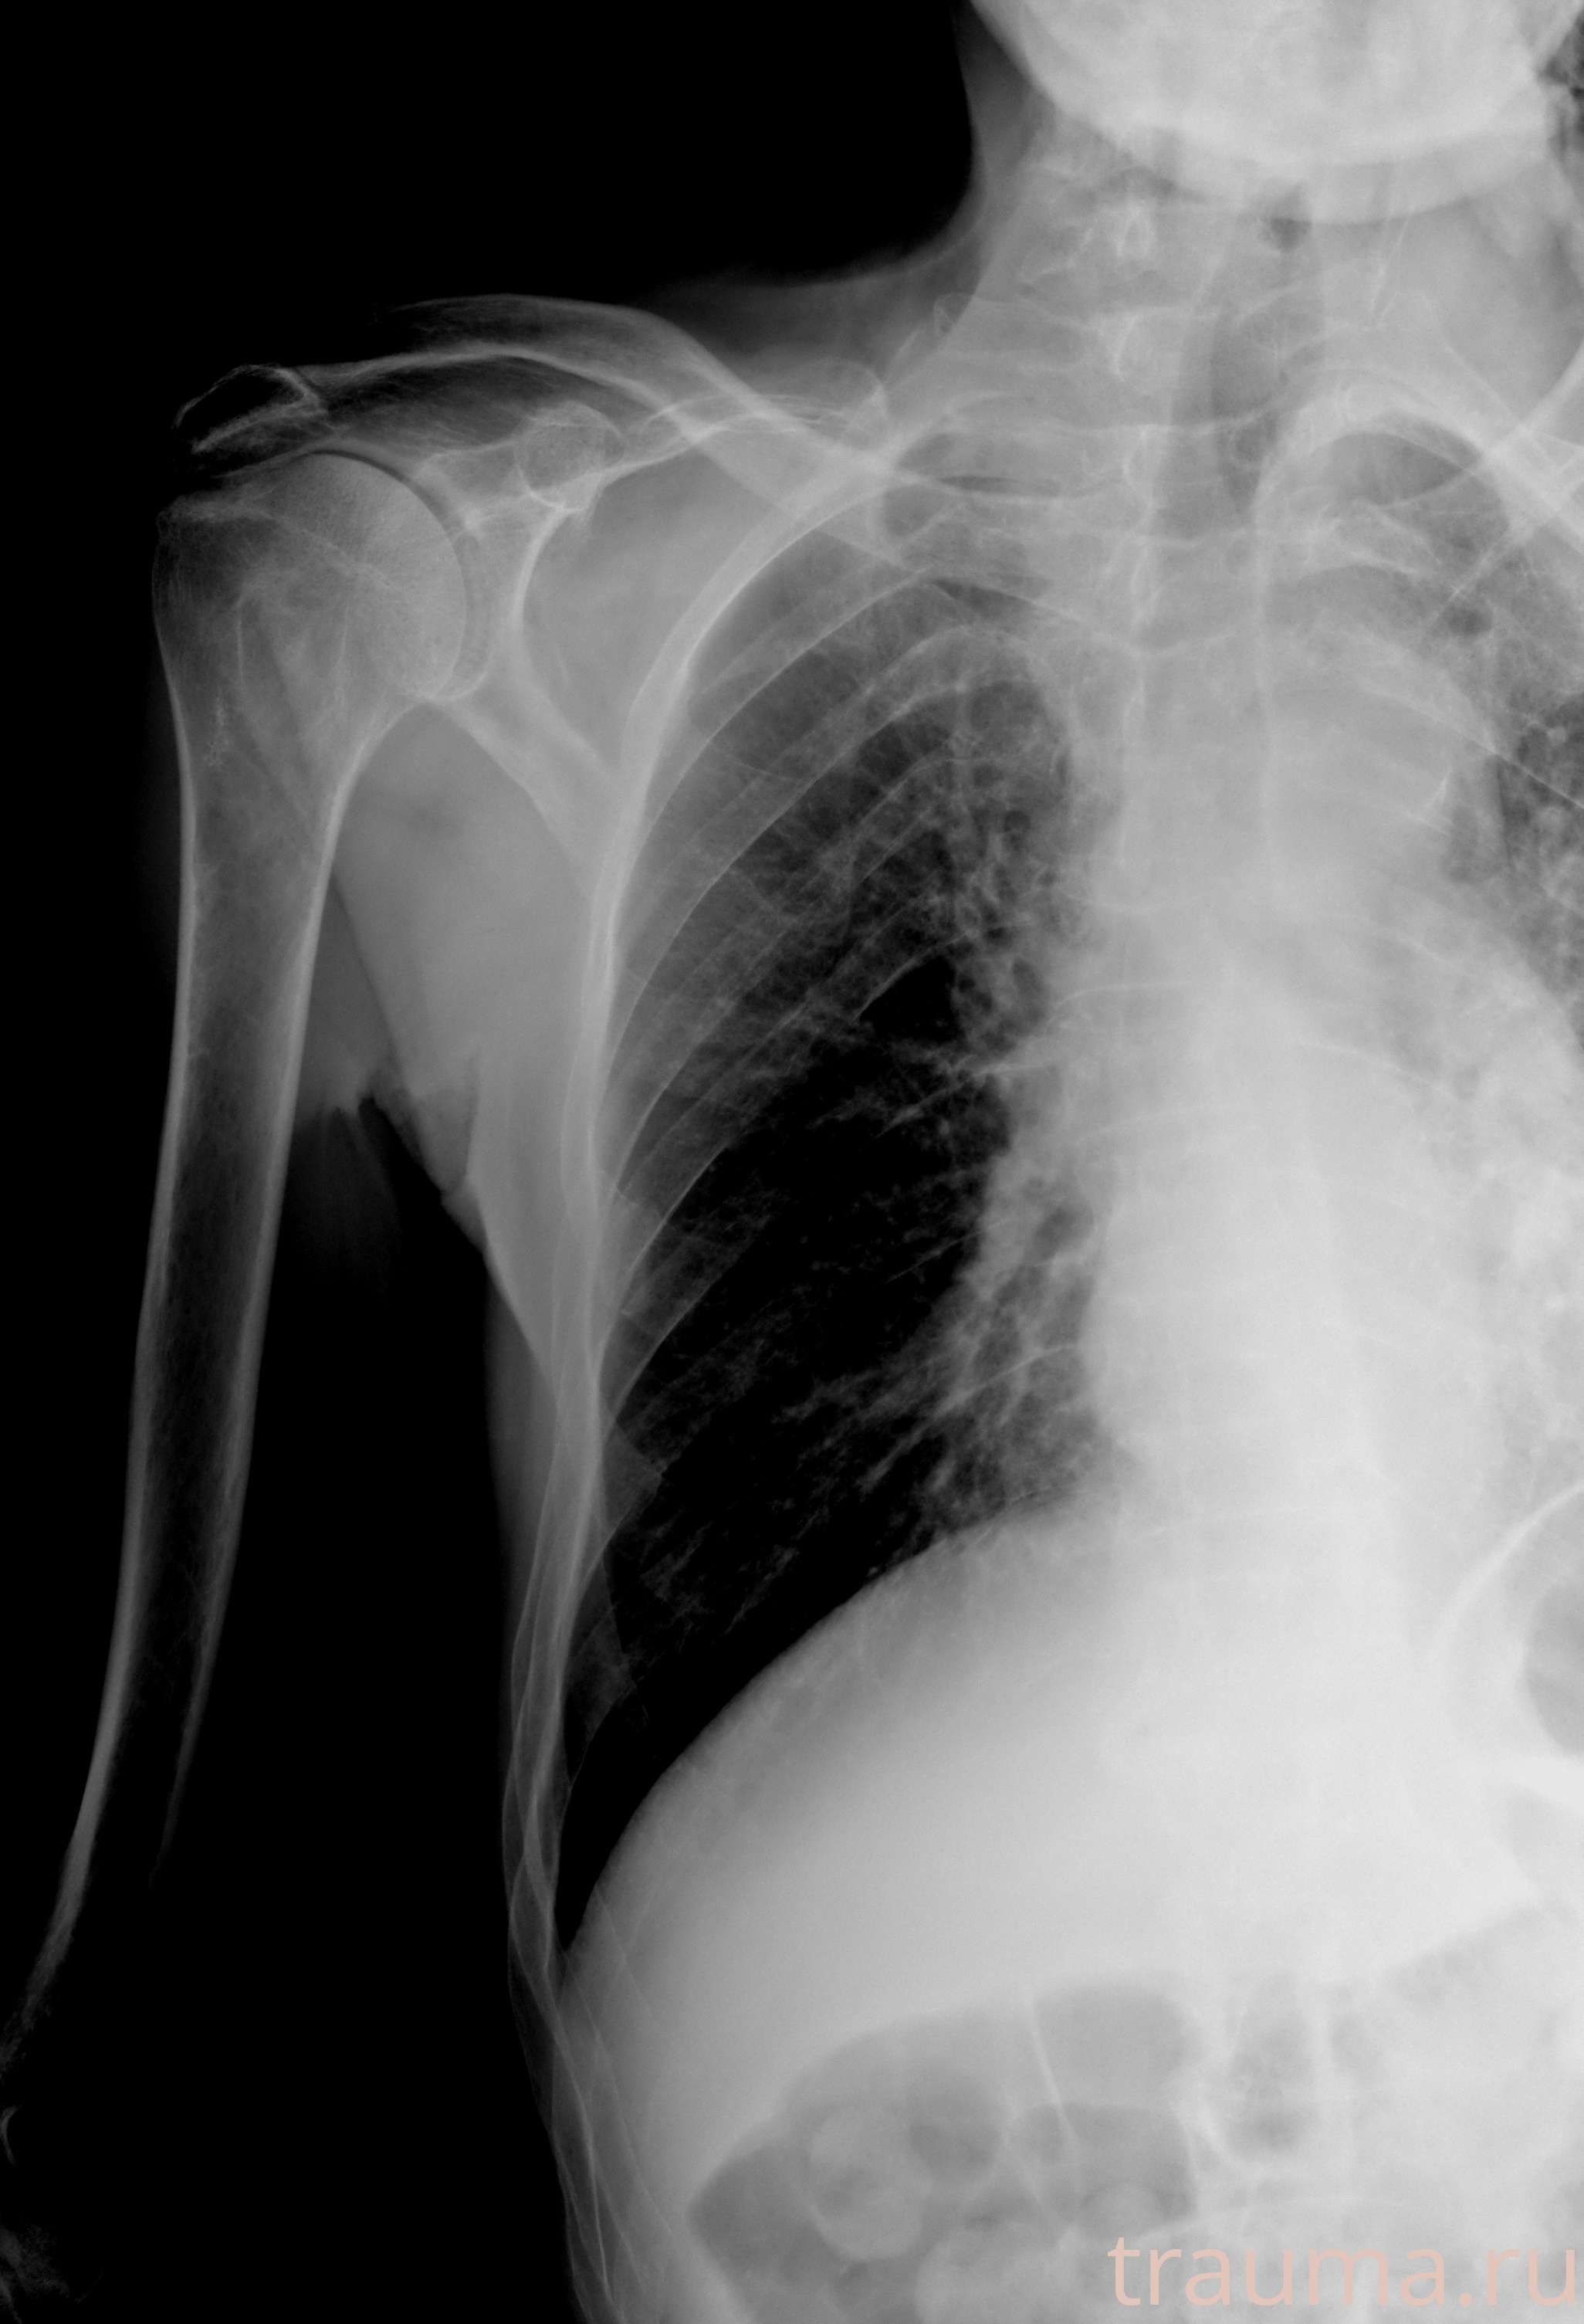

Рентгенограммы

Рентген на дому: по вашему адресу приезжает врач-рентгенолог, травматолог-ортопед с мобильным рентгеновским аппаратом, проводит диагностику травмы или заболевания, делает необходимые рентгенограммы, дает рекомендации по дальнейшему лечению. Получить качественные снимки в домашних условиях возможно благодаря уникальной методике, разработанной МосРентген Центром для института  Склифосовского